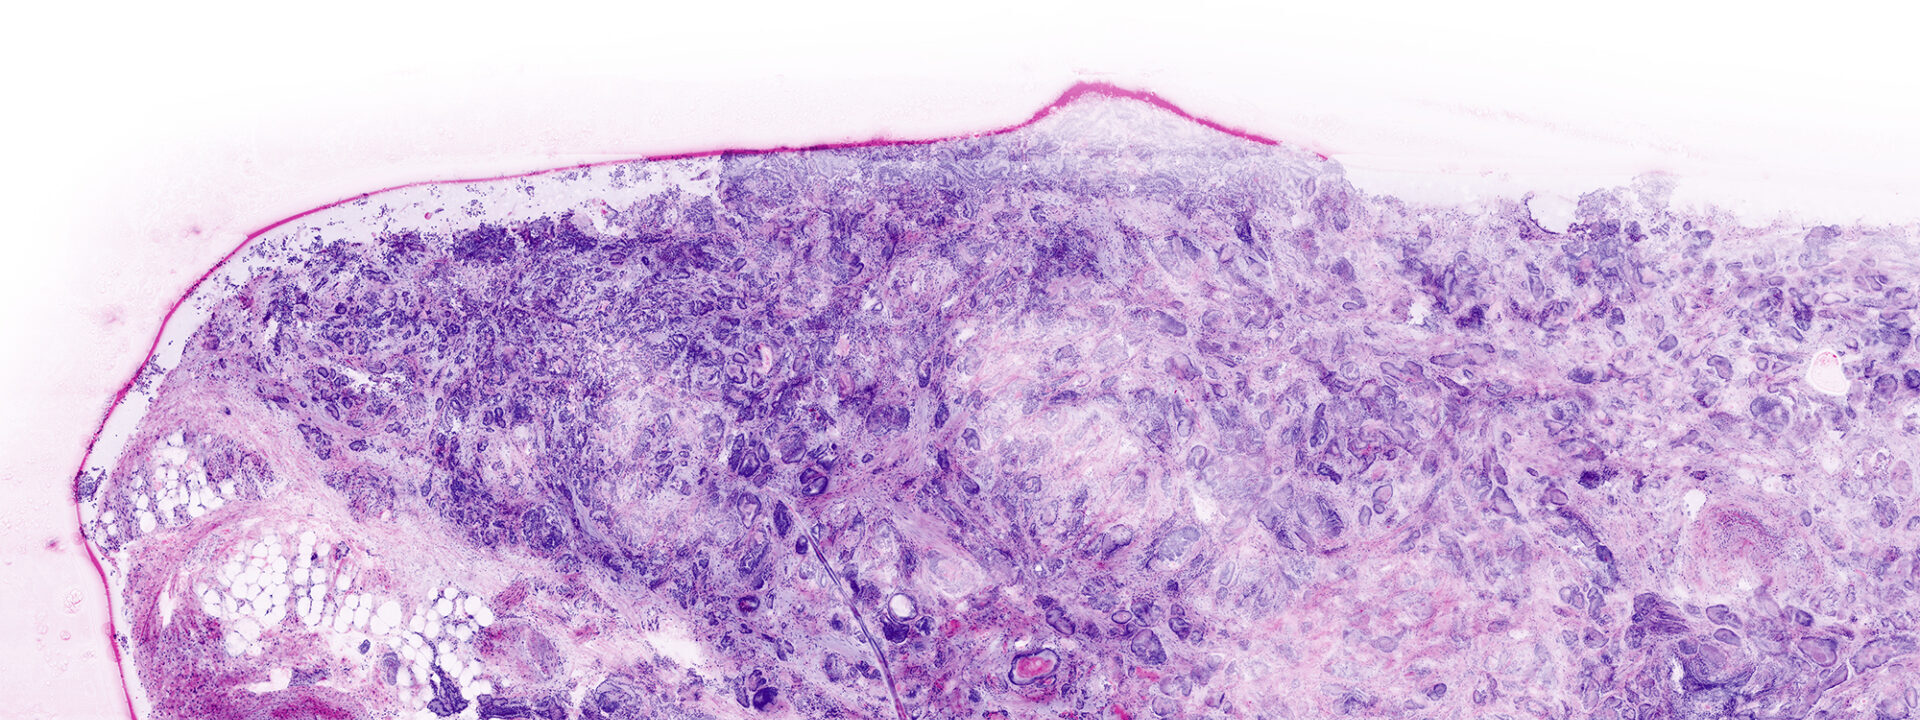

VivaScope Ex Vivo technology allows for direct pathological assesment during surgery. Like H&E staining, VivaScope images are generated from two components. Two lasers of different wavelengths create two distinct images, a fluorescence image and a reflectance image. Both signals are scanned simultaneously and are used to create pseudo-colored images. The device’s software uses an algorithm to translate the acquired image information into colors that resemble H&E.

Images courtesy of Dr Javiera Pérez-Anker. Basal cell carcinoma; imaged with the VivaScope 2500 (left) and after H&E staining (right).

The VivaScope technology is based on confocal microscopy (CLSM) and acquires images of superb optical resolution and contrast. The VivaScope 2500 images allow seamless zoom with up to 500x magnification and a great sample size.